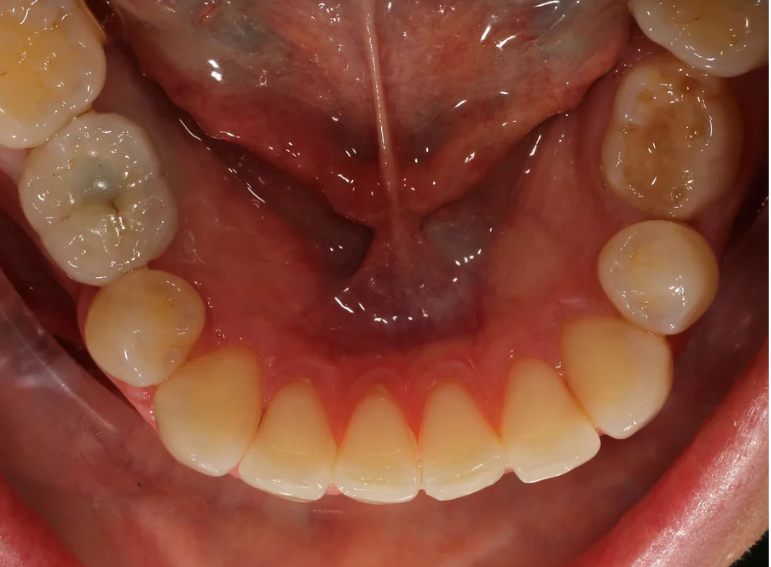

Missing lower premolar due to hypodontia replaced with an implant.